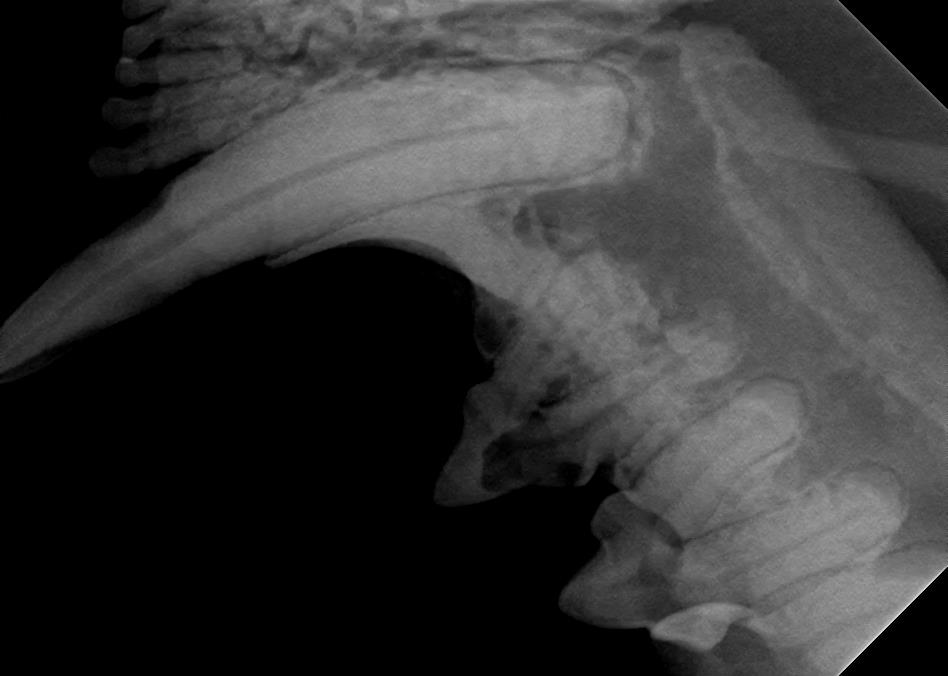

Examples of healthy teeth:

At A Couple of Vets, our animal hospital staff is well-versed in the latest dental cleaning techniques to remove plaque and tarter from the teeth’s surface as well as from below the gum line. We perform dental x-rays at every cleaning to ensure that the teeth are completely healthy. They may look good on the surface, but many problems occur below the gum line and are only visible with x-rays.